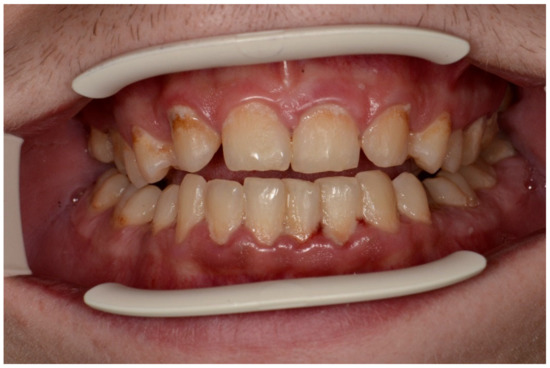

The mean API score among the subjects was 63.47% (SD = 22.78) and ranged between 22 and 100%. The mean value of the index for the control group was 68.75% (SD 21.46) and ranged from 19 to 100%. The p > 0.05, therefore the study and control groups did not differ significantly from the API value. The median value of the API index for the study group was 65 and 68.5 for the control group. Table 3 and Figure 1 present the API score and the API score pictured according to interpretation values. Figure 2, Figure 3 and Figure 4 show the clinical situation of the participants. The API values did not have a normal distribution in the analyzed groups (p < 0.05 from the Shapiro–Wilk test), so the analysis was carried out using the Mann–Whitney test.

Figure 3. Man, 28 y.o. API = 100%. Calculus and dental plaque deposits. Dental Biofilm-induced Gingivitis. Teeth discoloration and superficial caries lesions.